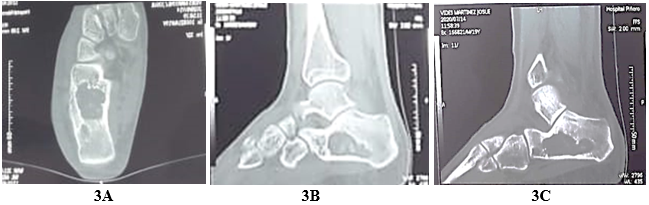

Standard chest x-ray: normal (Figure 1). Anteroposterior (AP) and lateral radiograph of the left ankle. Calcaneus with a delimited circular radiolucent image, with an increase in volume in the soft tissues (Figure 2). Laboratory studies showed positive CRP, increased RSV with lymphocytosis. A vascular Doppler echo of the left lower limb was performed due to the edema, which indicated no vascular compromises. The computed tomography of the left foot shows a hypodense osteological-type lesion, affecting two-thirds of the calcaneus, thinning of the cortices and involvement in the support area of the calcaneus (Figure 3).

Figure 3A Coronal section of computed tomography of the left foot shows a hypodense osteological-type lesion.

Figure 3B&3C Sagittal section of computed tomography shows two thirds of the calcaneus, thinning of the cortices and involvement in the support area of the calcaneus.